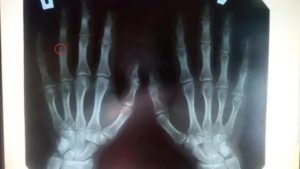

Но существует единственный и точный метод узнать это – сделать рентгеновский снимок кисти руки либо крайней трети предплечья. Если на снимке зоны роста светлые, значит они еще открыты. Если выглядят как и все остальные кости, значит закрыты.

Специалист с одного взгляда сможет определить закрыты либо открыт зоны роста и дать Вам точный, исчерпывающий ответ.